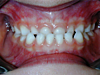

Cas 2

Enfant de 8 ans présentant un important décalage horizontal entre les 2 mâchoires corrigé avec un appareil amovible.